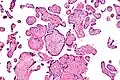

| Micrograph of villitis of unknown etiology. H&E stain. | |

Villitis of unknown etiology (VUE), also known as chronic villitis, is a placental injury. VUE is an inflammatory condition involving the chorionic villi (placental villi). VUE is a recurrent condition and can be associated with intrauterine growth restriction (IUGR). IUGR involves the poor growth of the foetus, stillbirth, miscarriage, and premature delivery.[1][2] VUE recurs in about 1/3 of subsequent pregnancies.[3]

VUE is a common lesion characterised by inflammation in the placental chorionic villi. VUE is also characterised by the transfer of maternal lymphocytes across the placenta.[2]

Histomorphologically, VUE is characterized by a lymphocytic infiltrate of the chorionic villi without a demonstrable cause. Plasma cells should be absent; the presence of plasma cells suggests an infective etiology, e.g. CMV infection.